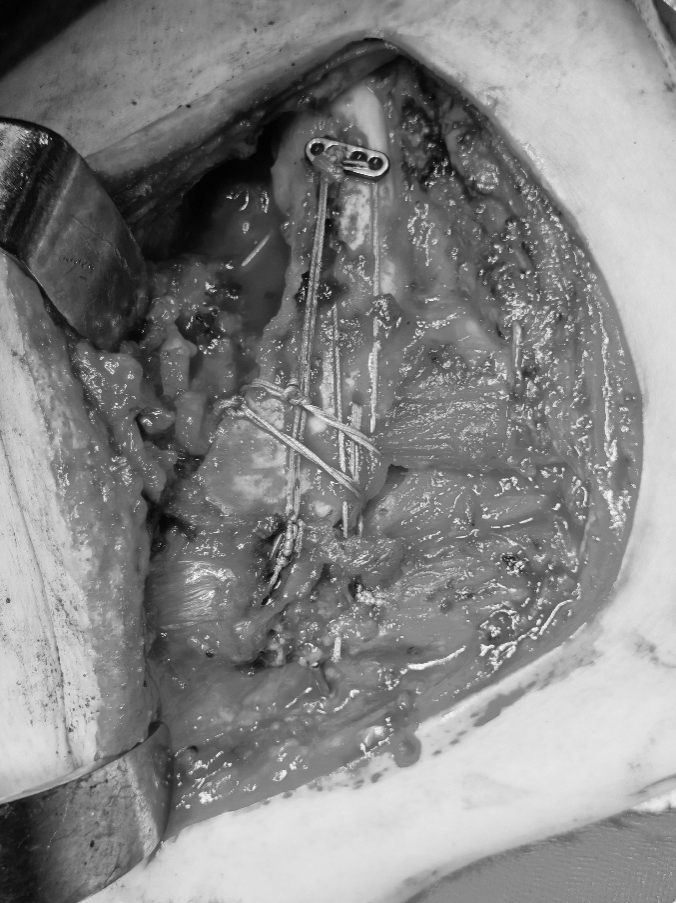

术中图

锁骨远端骨折合并肩锁关节脱位的治疗难点在于既要稳定骨折端,又要精准复位肩锁关节。长期以来,钩钢板一直是该类损伤的首选手术方案,但其局限性较为突出。首先,钩钢板植入过程中易损伤肩峰周围软组织;其次,术后异物感明显,肩关节活动受限,影响功能恢复;最后,患者需接受二次手术取出钢板,不仅增加手术风险,也加重心理负担。针对这些问题,该患者手术采用创新悬吊缝合桥技术,是在肩锁关节脱位手术中喙锁悬吊系统的基础上创新改良而成。术中分别于喙突基底部、锁骨近端、锁骨远端及肩峰放置带袢钛板,并使用缝线交错连接各钛板,构成对骨折端起弹性固定作用的缝合桥。该技术以喙突为基底,通过上方多个固定点下压复位骨折端及肩锁关节,形成稳定的固定结构。